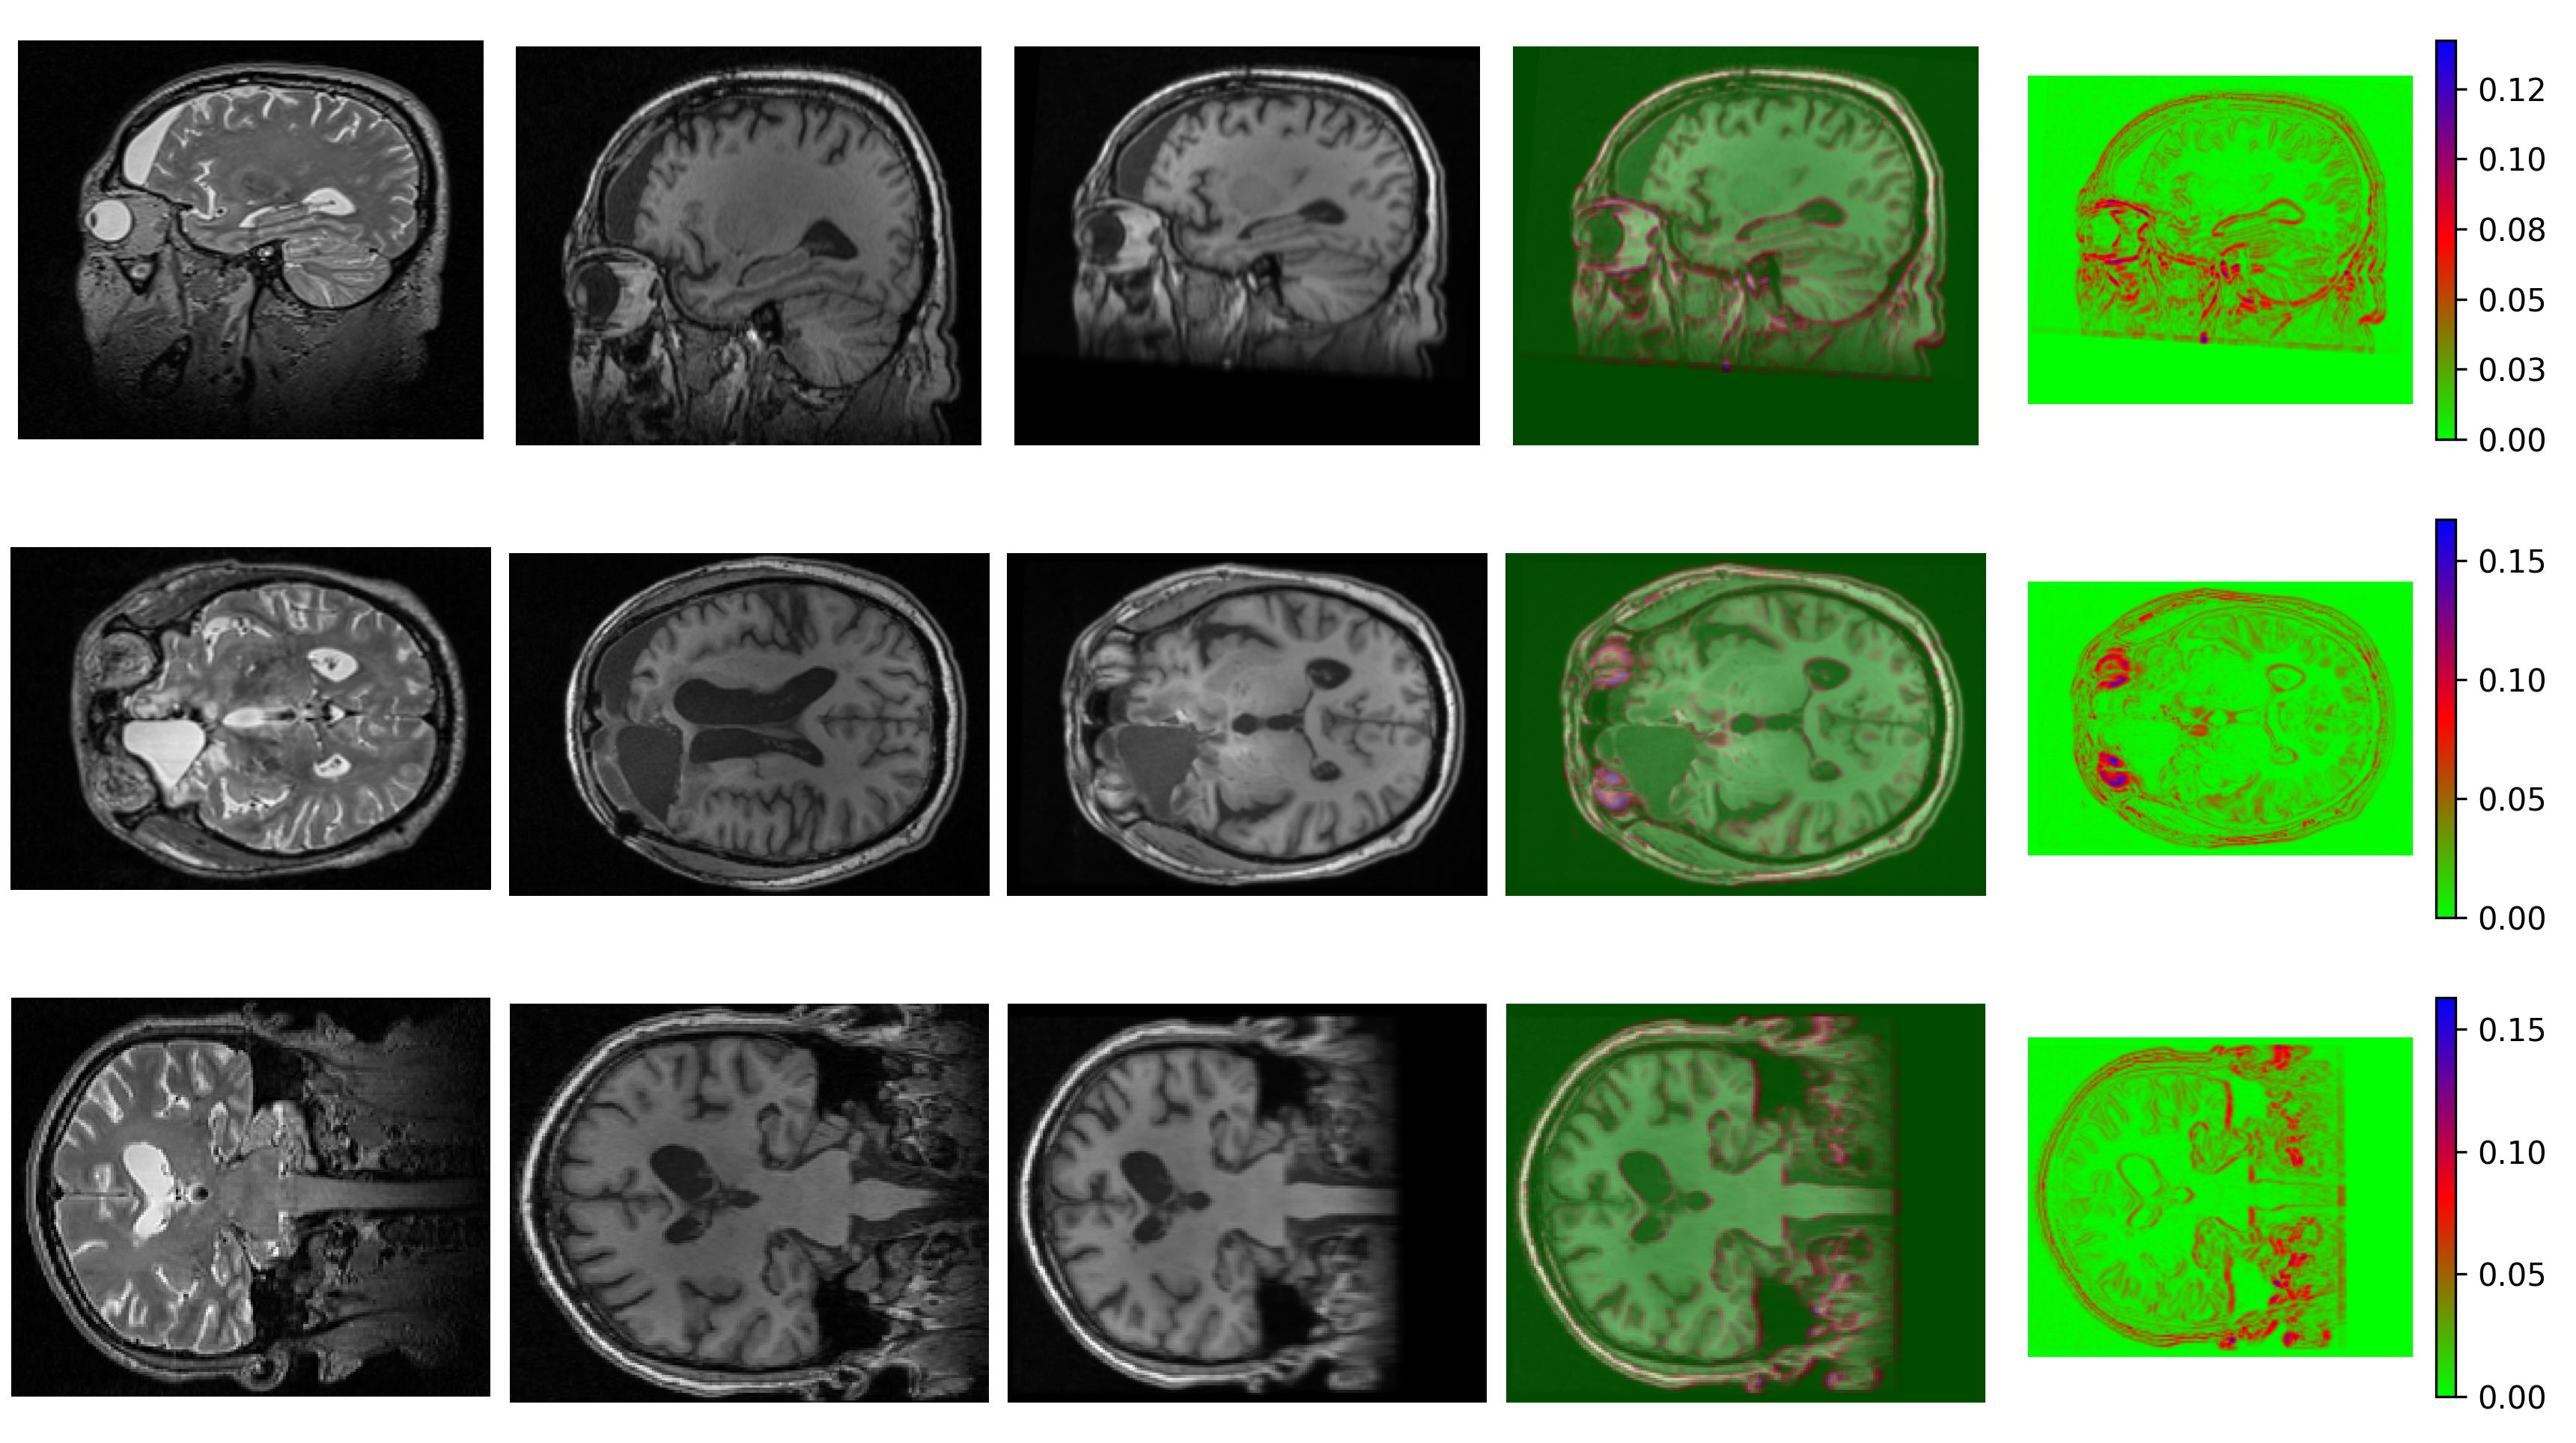

The table 3 illustrates the performance of different methods in terms of Dice similarity coefficients for WM-GM (white-gray matter) and brain mask for rigid registration tasks with skull stripping. Among the methods evaluated, ours Reg-LEdge-Model variant-4 achieves the highest scores, with a Dice WM-GM of 0.757 and a Dice brain mask of 0.912, indicating superior registration accuracy. On the other hand ANTs also demonstrate strong performance, particularly in the brain mask 0.911 however, Dice WM-GM 0.726 is not comparable with our method Reg-LEdge-Model variant-4. Reg-LEdge-Model variant-2 and Reg-LEdge-Model variant-3 perform better, particularly in the brain mask task, with Dice scores of 0.851 and 0.845, respectively, though their WM-GM scores are slightly lower at 0.735 and 0.734.The methods VM-affine, TransMorph-affine, show competitive but lower performance compared to our methods, with Dice WM-GM scores ranging from 0.724 to 0.731 and Dice brain mask scores between 0.792 and 0.812. Reg-LEdge-Model variant-1 achieves a Dice WM-GM score of 0.741 and a Dice Brain Mask score of 0.803, indicating a balanced performance but not as high as the main Reg-LEdge-Model variant-4 method. Figure 15 shows the visual comparison of different methods and Figure 16 shows uncertainty estimation.

For elastic registration, we initially used our method Reg-LEdge-Model variant-4 (rigid registration) to perform affine registration on all images. These affine-registered images were then used as input for our proposed Reg-LEdge-U-Model variants of non-rigid registration, allowing us to compare their performance with other methods. The table 4 presents the comparison of various registration methods based on their Dice similarity coefficients for WM-GM (white-gray matter) segmentation. Among the methods evaluated, LEdge-U-Model variant-4 achieves the highest performance with a Dice WM-GM score of 0.798, indicating the most accurate registration. Following closely are LEdge-U-Model variant-3 and LEdge-U-Model variant-2 with Dice scores of 0.791 and 0.783, respectively, showcasing the effectiveness of our proposed variants in improving segmentation accuracy. LEdge-U-Model variant-1 also performs well, with a Dice score of 0.774, slightly surpassing TransMorph which has a score of 0.772. VoxelMorph show competitive performance with Dice scores of 0.769 and 0.761, respectively. ViT-V-Net on the other hand, exhibit lower accuracy with Dice scores of 0.746. SyN and LDDMM secure Dice score of 0.766 and 0.754 respectively.These results underscore the superiority of our proposed methods in enhancing registration accuracy, as reflected by their higher Dice WM-GM scores compared to other methods in the table. Figure 20 shows qualitative results and Figure 21 represents the uncertainty estimation of the best performing proposed Reg-LEdge-U-Model variant-4.